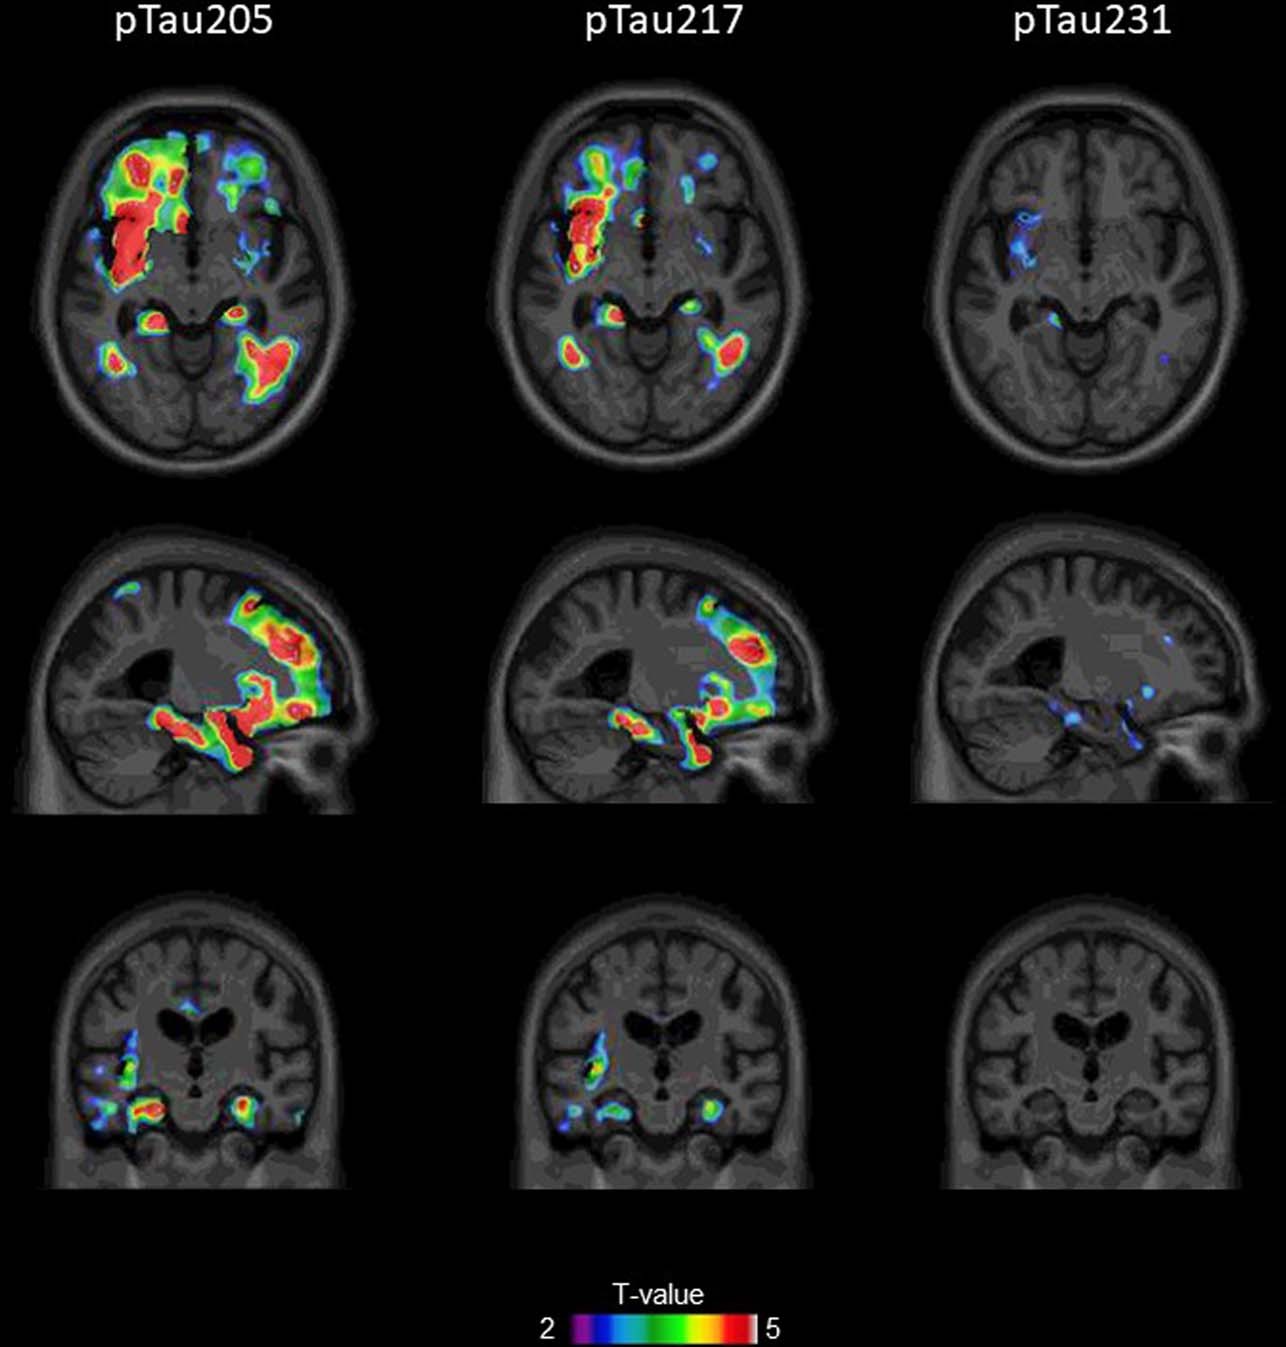

Extended Data Fig. 7: Voxel-wise associations of p-tau205, p-tau217 and p-tau231 with Tau PET uptake.

Adjusted for multiple comparisons maps depict the results of the association between plasma biomarkers and Amyloid PET at the voxel level (n=51). Voxels with T-value>3 have a significant association between the variables evaluated. P-tau181 is not included in the figure since it did not survive adjustment for multiple comparisons.